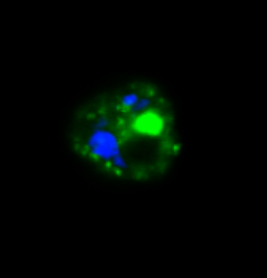

Malaria parasite expressing ARF-GFP